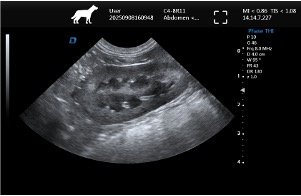

| Imaging Quality | Clear 2D, stable grayscale, optional Color Doppler for abdominal, cardiac, reproductive exams | Ensure system covers most frequent clinical exams |

Common Clinical Applications

▸ Abdominal examinations (liver, kidneys, bladder, spleen)